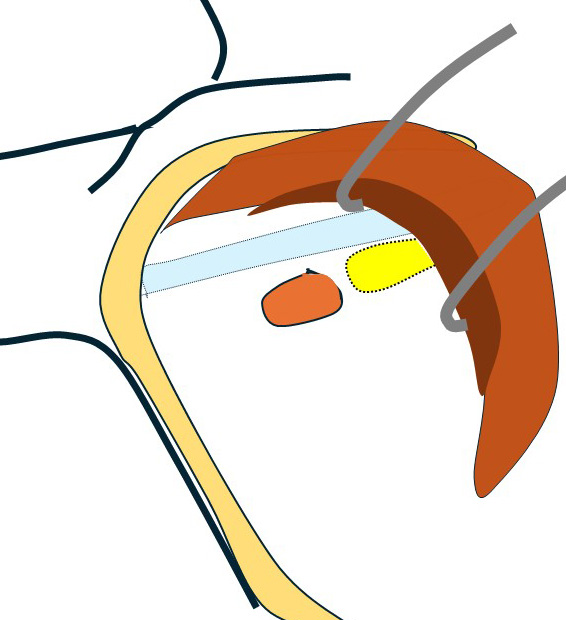

これらエコーをつなぎ合わせたもの

リンパ節は黄色に表現

大胸筋(茶色)の裏に小胸筋(こげ茶色)

大胸筋の外側にリンパ節2つ、大胸筋の裏にリンパ節1個 これら3個がレベルⅠ

小胸筋裏にリンパ節(これが最大で2㎝)これがレベルⅡ

それより内側(奥)に比較的小さいリンパ節2個 これらがレベルⅢ

色分けすると 赤とオレンジ:レベルⅠ、 黄色:レベルⅡ 、赤(周囲に点線の小さいもの):レベルⅢ